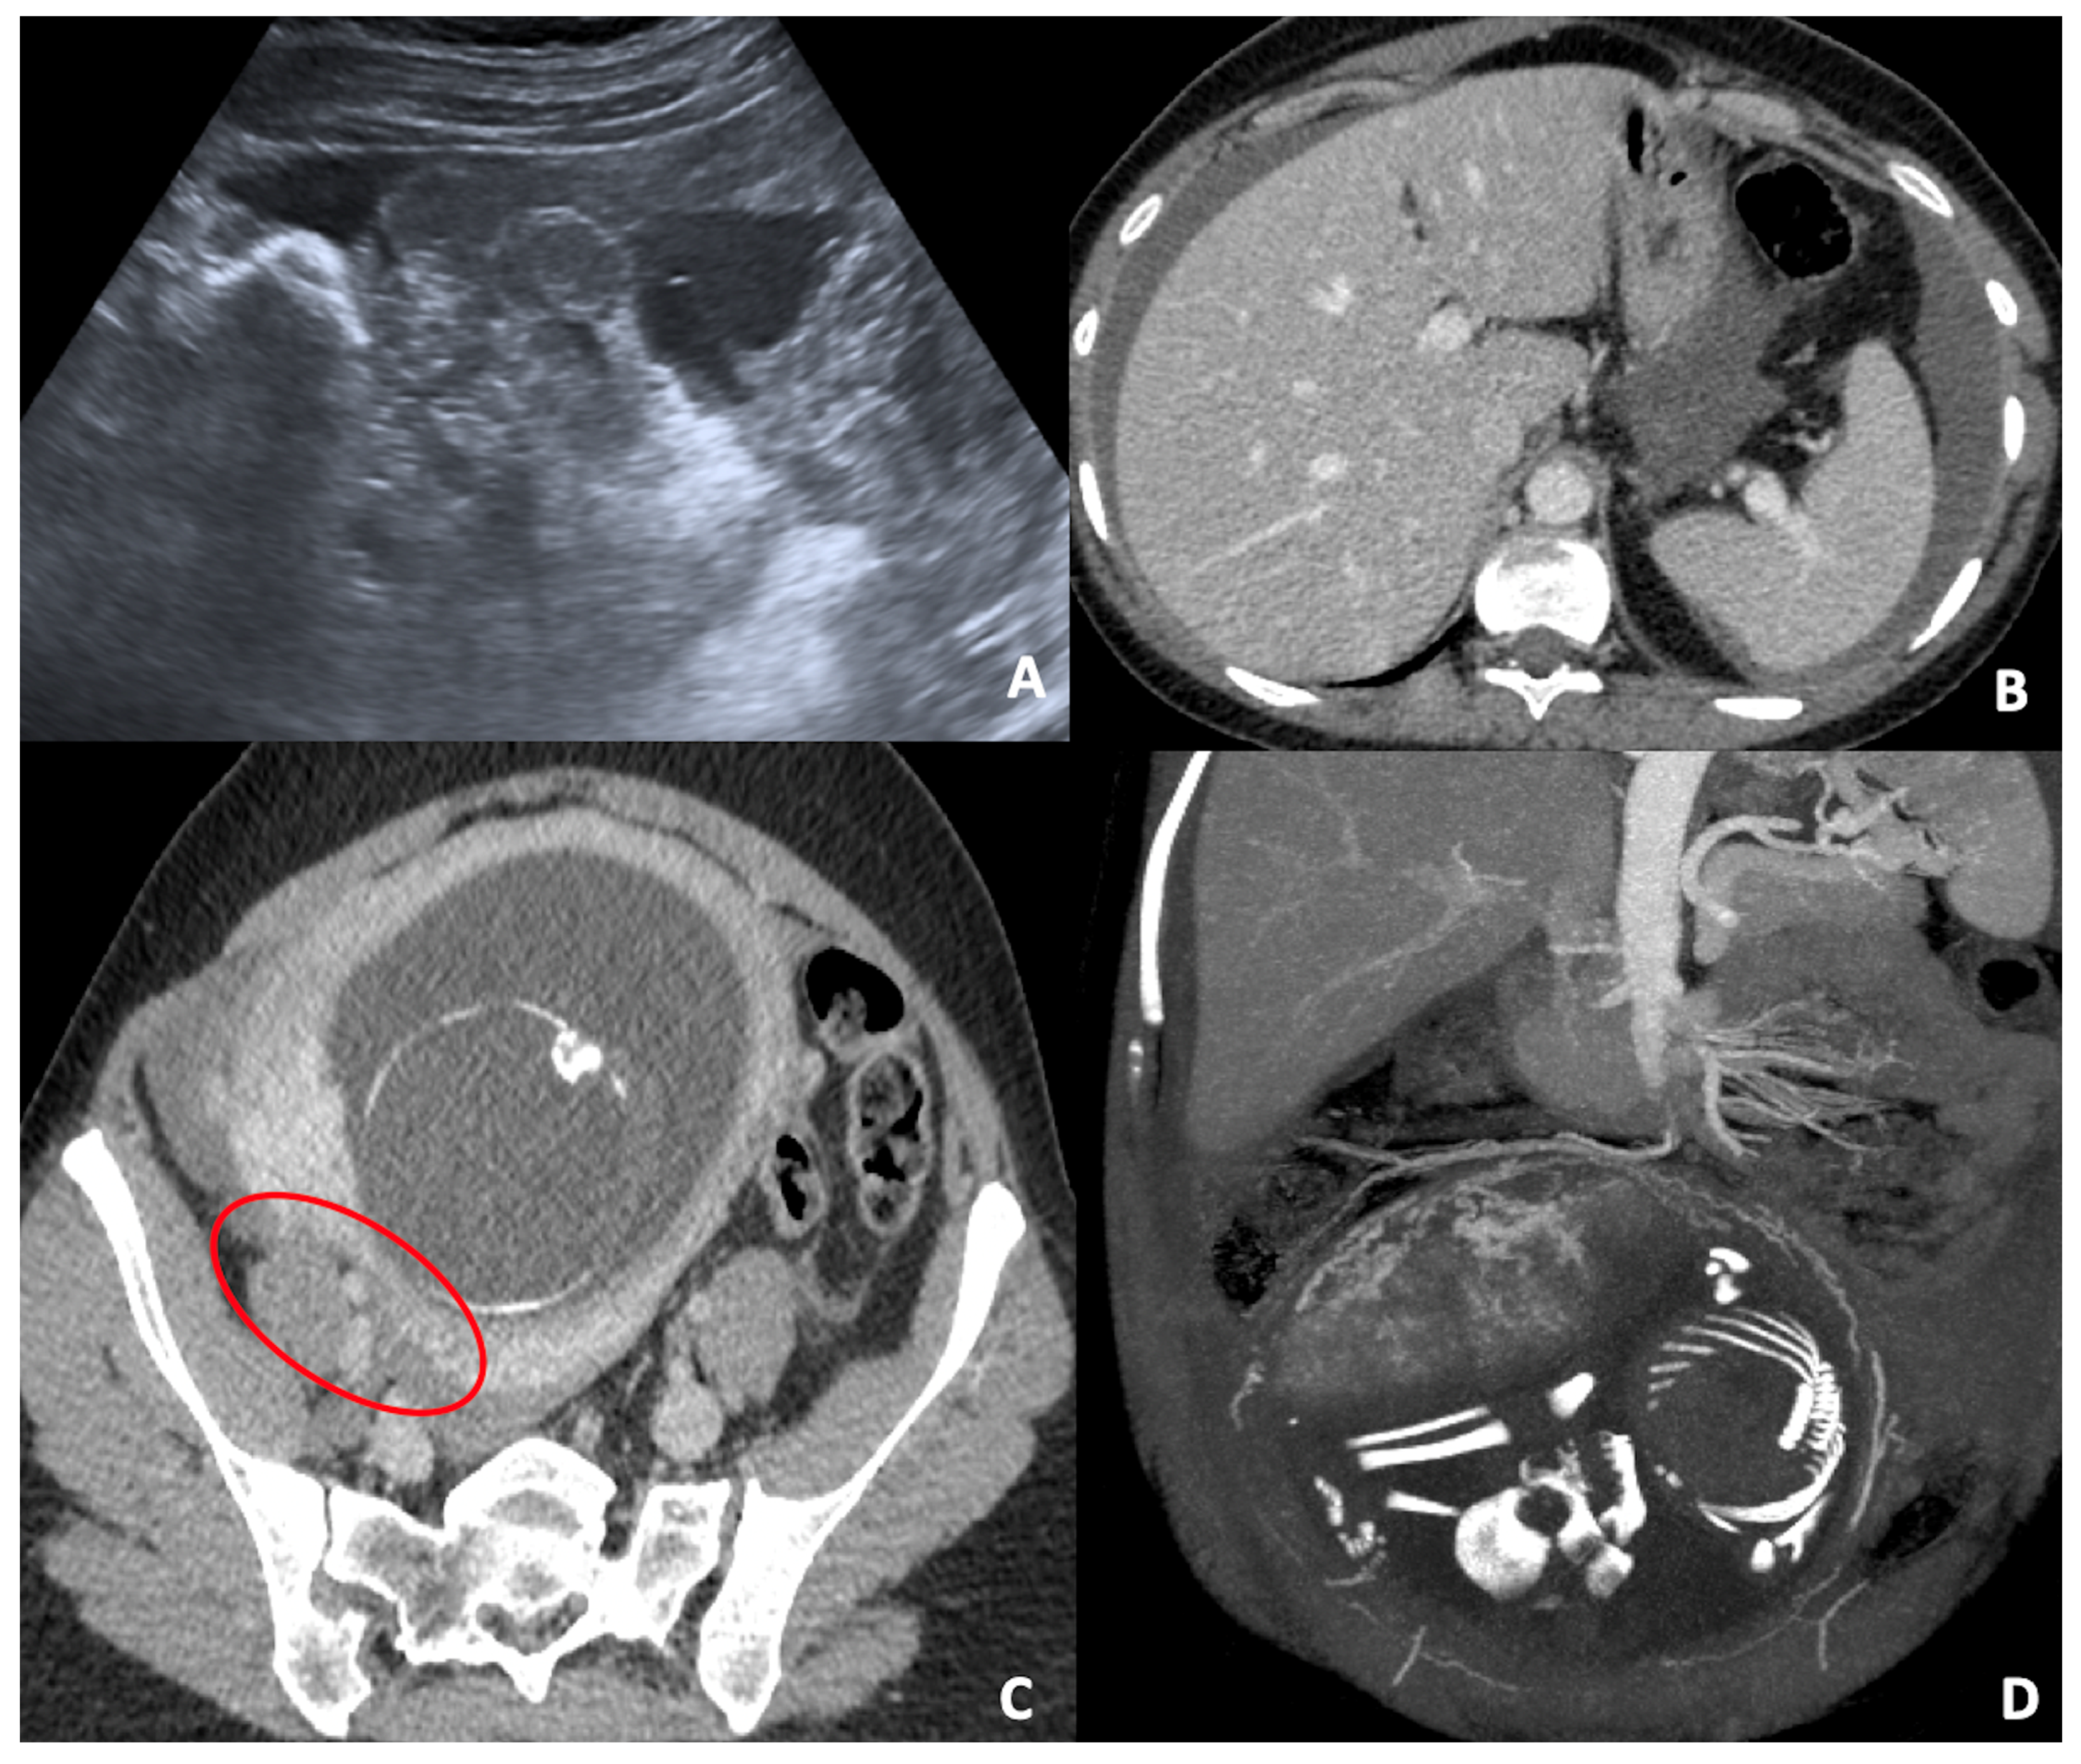

3.1. Adnexal Masses or Ovarian Cyst

- Lee, S.J.; Kim, Y.-H.; Lee, M.-Y.; Ko, H.S.; Oh, S.; Seol, H.-J.; Kim, J.W.; Ahn, K.H.; Na, S.; Seong, W.J.; et al. Ultrasonographic evaluation of ovarian mass for predicting malignancy in pregnant women. Gynecol. Oncol. 2021, 163, 385–391. [Google Scholar] [CrossRef] [PubMed]

- Lee, S.J.; Oh, H.R.; Na, S.; Hwang, H.S.; Lee, S.M. Ultrasonographic ovarian mass scoring system for predicting malignancy in pregnant women with ovarian mass. Obstet. Gynecol. Sci. 2022, 65, 1–13. [Google Scholar] [CrossRef]

- Fruscio, R.; de Haan, J.; Van Calsteren, K.; Verheecke, M.; Mhallem, M.; Amant, F. Ovarian cancer in pregnancy. Best Pract. Res. Clin. Obstet. Gynaecol. 2017, 41, 108–117. [Google Scholar] [CrossRef]